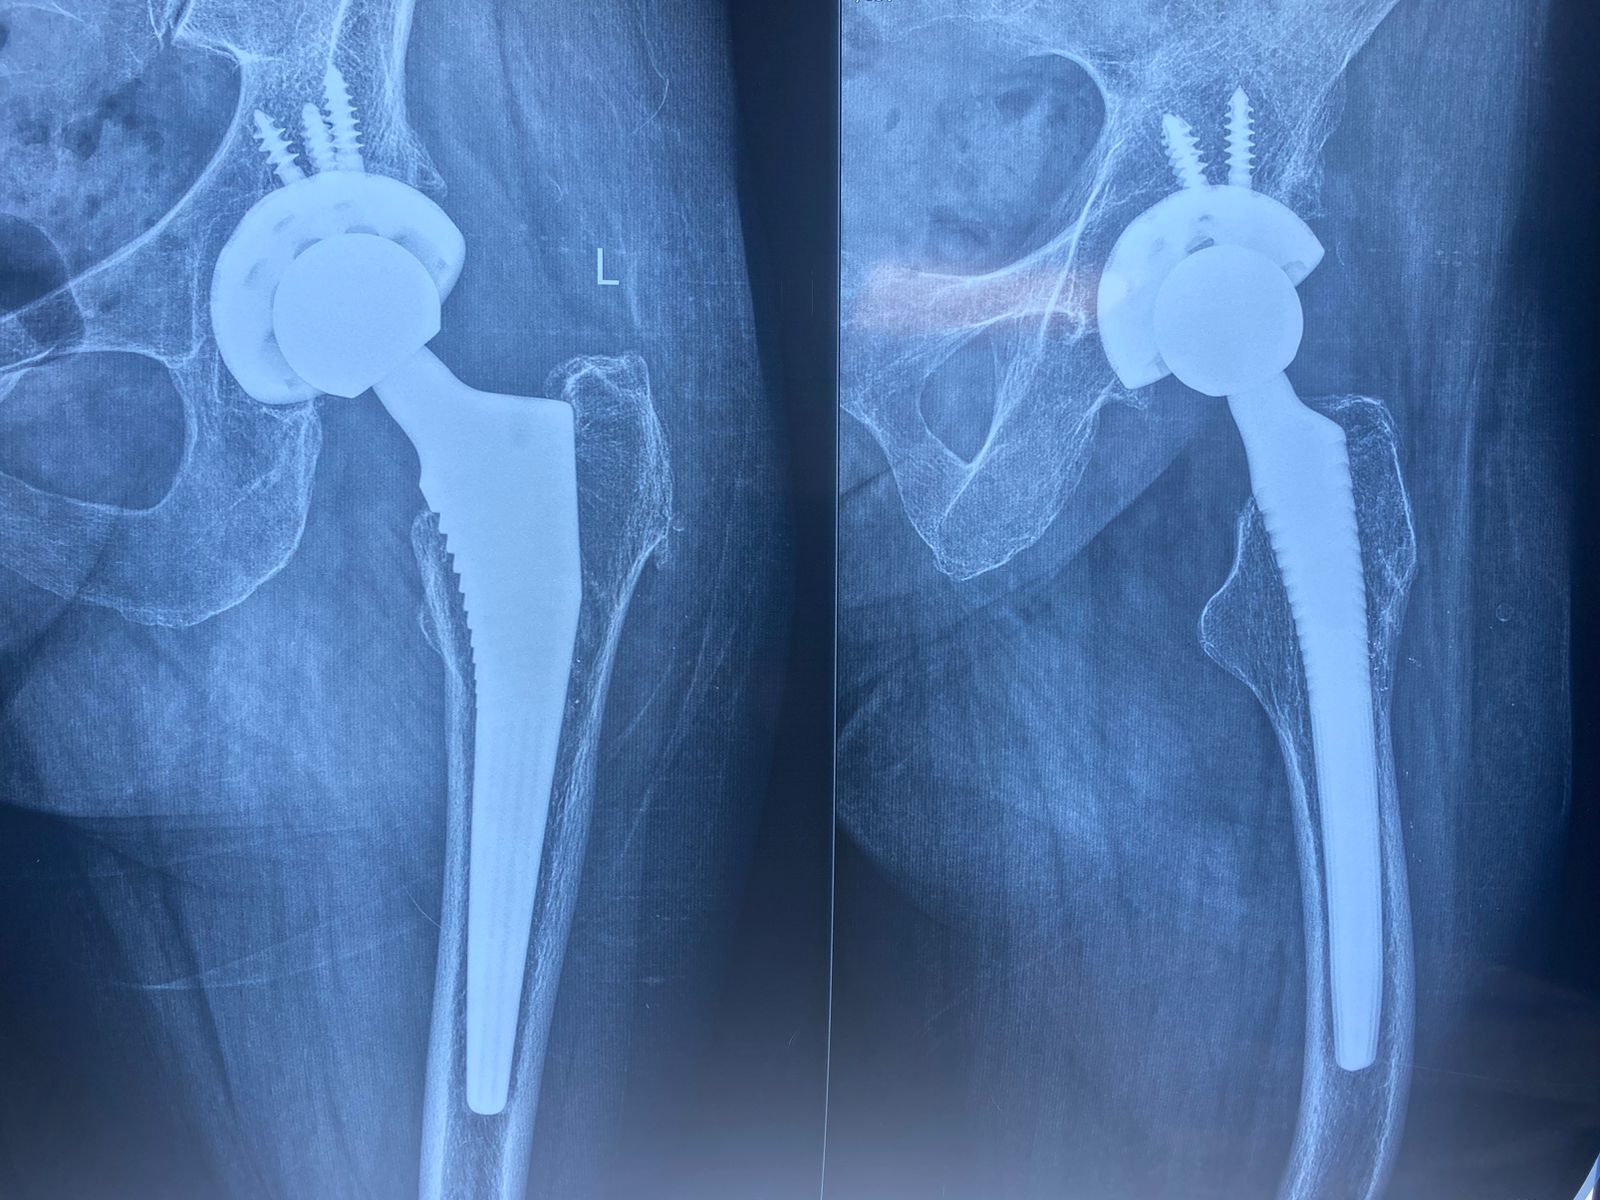

عام ٢٠٢٤ كانت الالام مع المشي اصبحت شديدة مما استدعى عمل تغيير كامل للمفصل